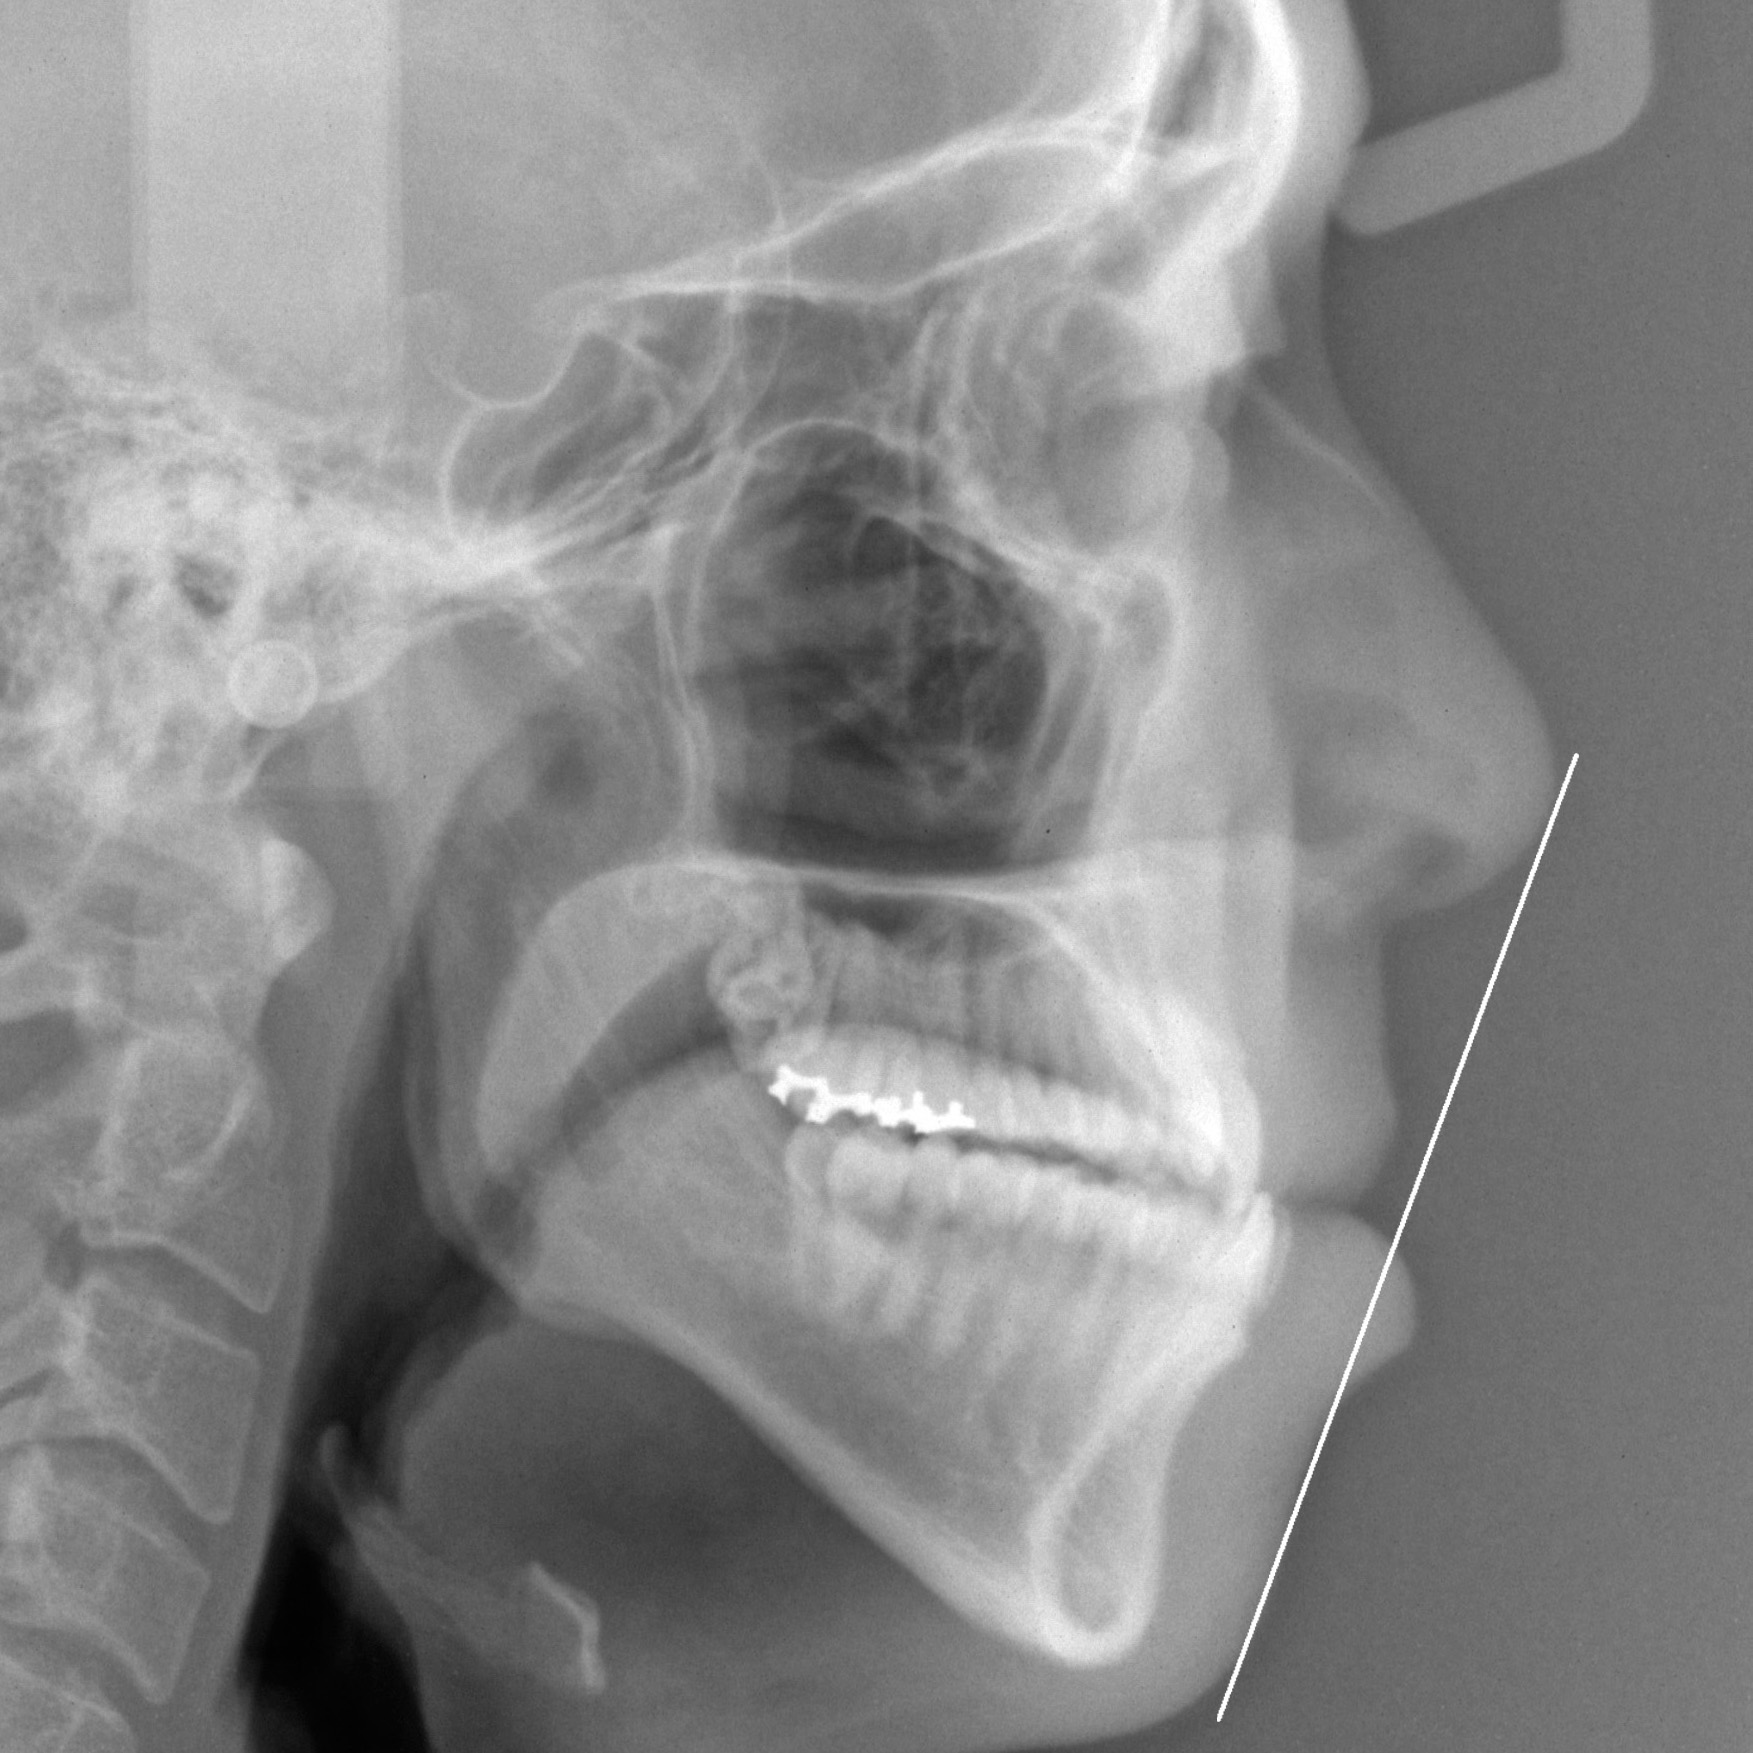

新着情報 150 治療前セファロ側面 – コピー Tweet 投稿日 : 2026年01月06日(火)カテゴリー : コメントを残す コメントをキャンセルメールアドレスが公開されることはありません。 * が付いている欄は必須項目ですコメント 名前 * メール * サイト 26歳 男性 「手術なしで 受け口を 治してほしい」(骨格的な要因を伴う 反対咬合) ≫